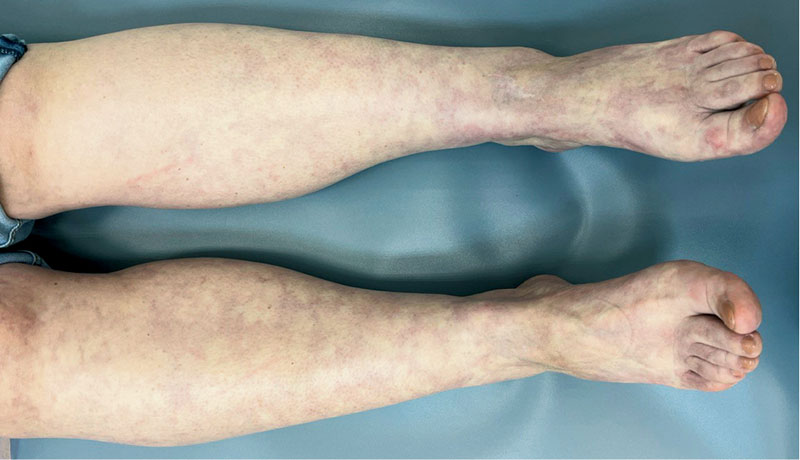

Рис. 6. Пациентка с ЛВ без язв до проведения комплексной терапии с применением НТАП

Рис. 7. Пациентка с ЛВ без язв после проведения комплексной терапии с применением НТАП

В обеих группах после проведенного лечения наблюдалась положительная динамика в виде исчезновения онемения и боли в нижних конечностях, активации заживления язвенных дефектов, уменьшения выраженности ливедо, но при присоединении к основной терапии процедур низкотемпературной аргоновой плазмы наблюдалось более выраженное улучшение со стороны кожного процесса у пациентов группы исследования по сравнению с группой контроля (рис. 4–14).